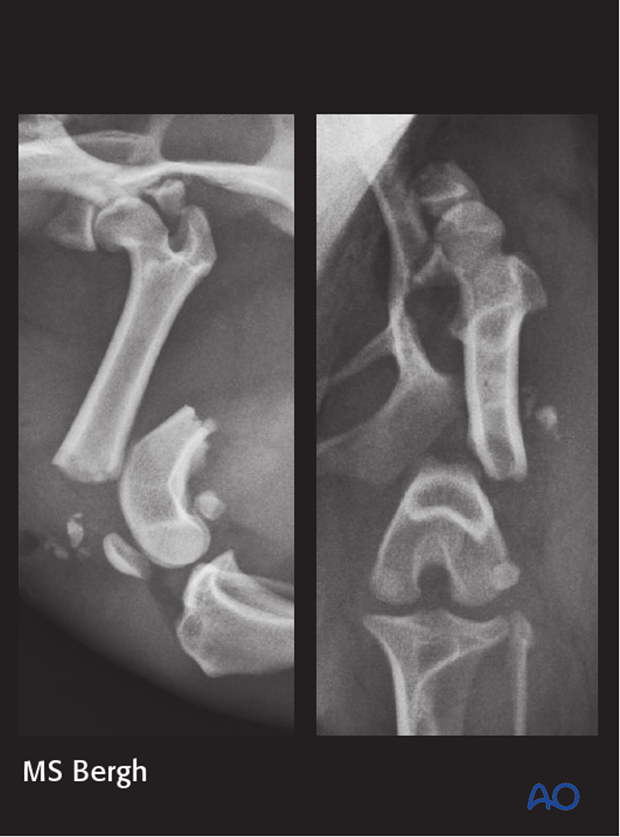

2-year-old small mixed breed dog presented from a shelter after being hit by a car, with a left grade 1 open 33-A1 fracture, comminuted acetabular fracture, and sacroiliac luxation.

The fracture was repaired using a reconstruction plate and a K-wire. Note the transcondylar distal screw placement.

A femoral head and neck excision was also performed.

The patient reportedly recovered well on telephone follow up but never returned for radiographs.